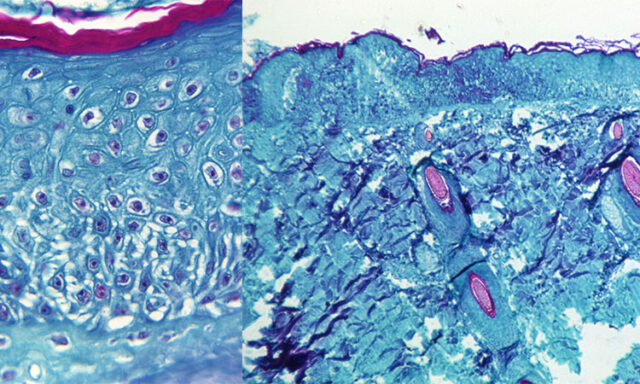

Как правило, заболевание начинается с общих симптомов, характеризующихся лихорадкой, миалгией (боль в мышцах), сильной головной болью, лимфаденопатией (опуханием лимфатических узлов), за которыми следует кожная эрупция, в основном на лице, которая распространяется на другие части тела.